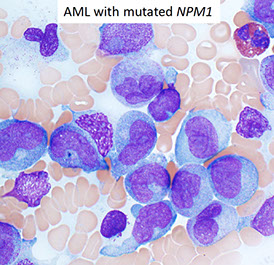

- Acute myeloid leukemia with mutated NPM1

- absensce of the specific cytogenetics abnormalities seen in AML with recurrent genetic abnormalities

MC in elderly

Usually have severe pancytopenia

May appear de novo or from an evolving MDS

________________________________

IHC: w chr 5/7 del get (+) CD34, 7, TdT

________________________________

Genes: del -5 and del -7 are MC

- If NPM1 mutation identified, diagnose as AML with NPM1 mutation (despite MLD)